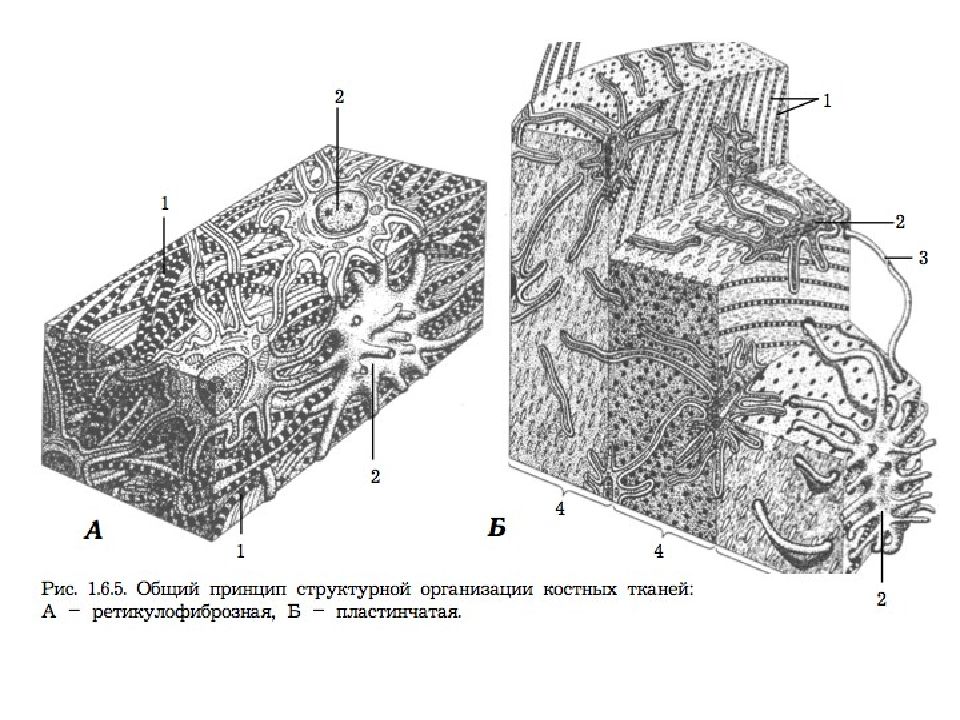

Структура грубоволокнистой костной ткани: наглядные примеры